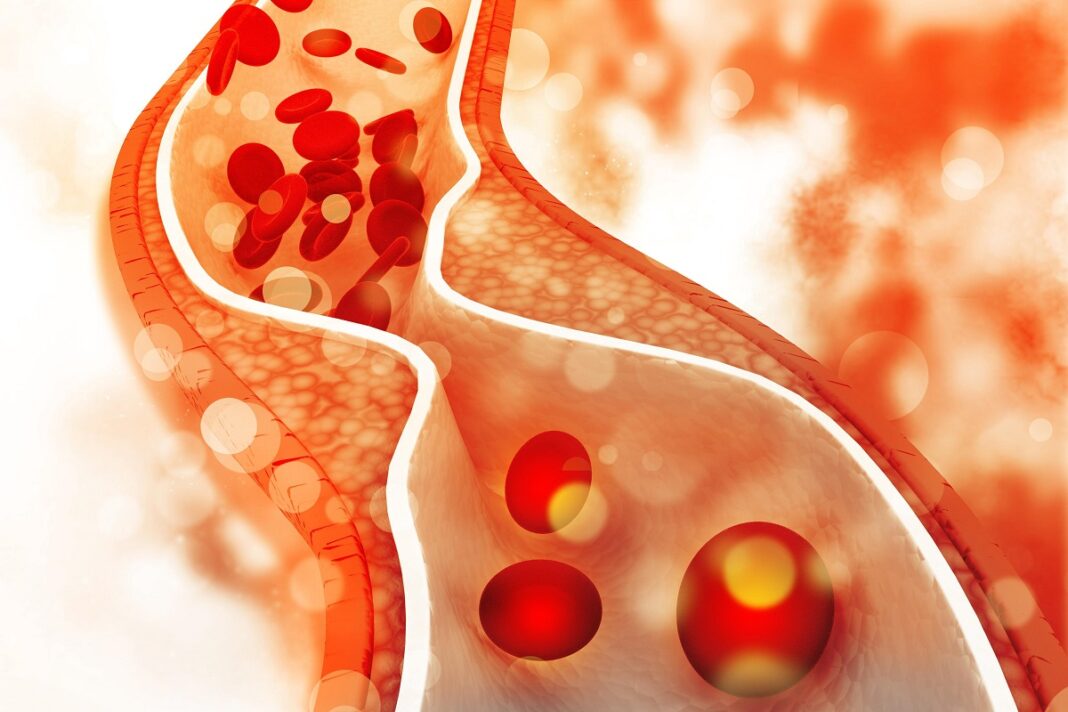

Η υψηλή χοληστερίνη μπορεί να προκαλέσει προβλήματα στο καρδιαγγειακό σύστημα. Μπορεί να προκαλέσουν καρδιακή προσβολή και εγκεφαλικό. Συνήθως την χοληστερίνη την ρυθμίζουμε με φάρμακα. Υπάρχουν όμως κι αλλοι τρόποι.

Η μέτρηση της χοληστερόλης γίνεται με εξέταση αίματος. Τα βέλτιστα -κατά προσέγγιση- επίπεδα χοληστερόλης στο αίμα (χιλιοστόγραμμα ανά δεκατόλιτρο, mg/dL) είναι:

Ένα συνολικό επίπεδο χοληστερόλης 200 mg/dL ή υψηλότερο ονομάζεται υπερλιπιδαιμία. Αυτό μπορεί να προκαλέσει αυξημένο κίνδυνο καρδιακής προσβολής ή εγκεφαλικού. Ευτυχώς, υπάρχουν πολλά βήματα που μπορείτε να κάνετε για να μειώσετε χωρίς φάρμακα τα επίπεδα χοληστερόλης και τον κίνδυνο επιπλοκών στην υγεία σας.